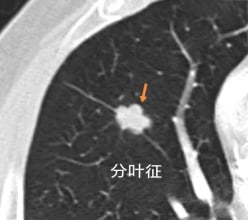

一、分叶征:不规则的生长边界

分叶征是指肺结节边缘呈现出不规则的、凹凸不平的波浪状轮廓,如同树叶的边缘。这种形态是由于肿瘤内部不同区域生长速度不一致,以及周围肺组织对肿瘤生长的阻碍所形成。根据凹陷的深度,分叶征可分为深分叶、中分叶和浅分叶。通常,深分叶征(弦弧距与弦长之比≥0.4)更强烈地提示恶性病变的可能性,是识别恶性肺结节的重要线索。